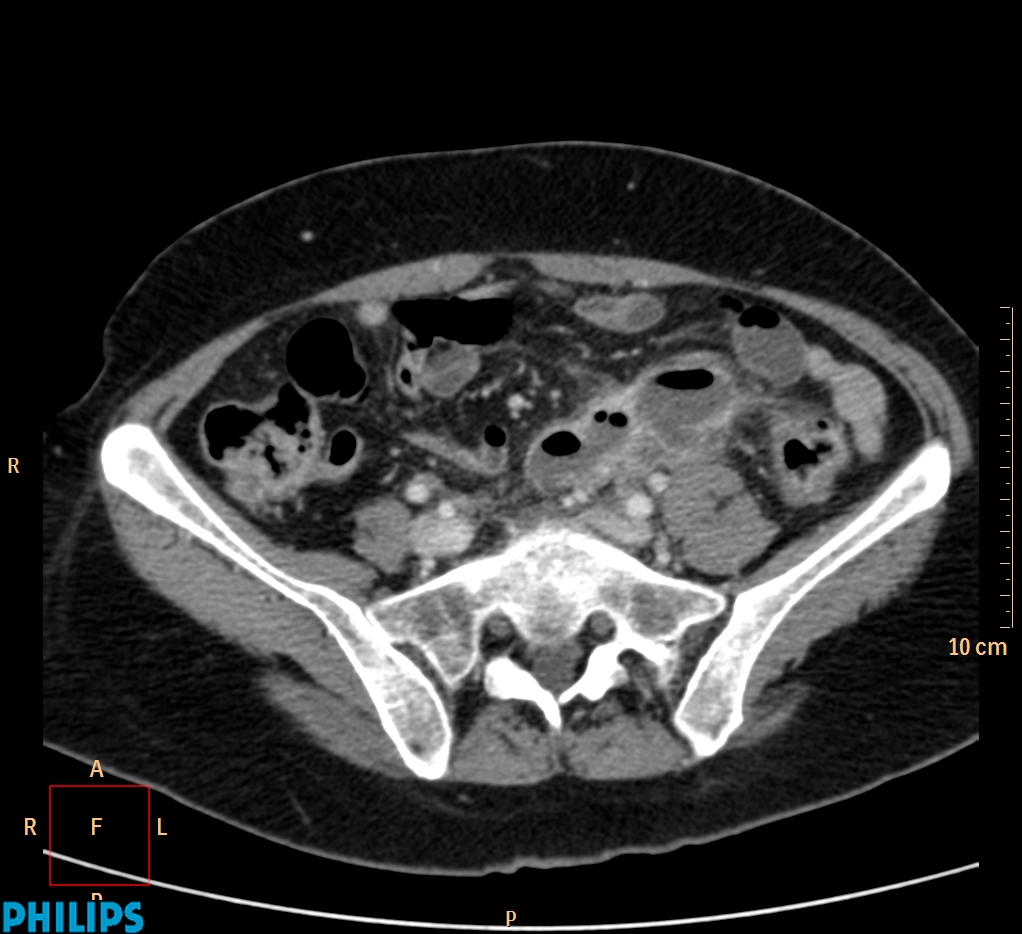

ΕΚΚΟΛΠΩΜΑΤΑ ΠΑΧΕΟΣ ΕΝΤΕΡΟΥ Posted by ΙΠΠΟΚΡΑΤΕΙΟ ΙΩΑΝΝΙΝΩΝ | Dec 16, 2020 | ΠΕΠΤΙΚΟ | 0 ΚΛΙΝΙΚΑ ΣΤΟΙΧΕΙΑ – ΙΣΤΟΡΙΚΟ υποτροπιάζοντες επαναλαμβανόμενοι πυρετοί κυρίως απογευματινές ώρες ΕΡΓΑΣΤΗΡΙΑΚΟΣ ΕΛΕΓΧΟΣ ΑΠΕΙΚΟΝΙΣΤΙΚΟΣ ΕΛΕΓΧΟΣ διακρίνονται τα αποστήματα στην ελάσσονα πύελο, καθώς και εκκολπώματα με εικόνα πάχυνσης του τοιχώματος του σιγμοειδούς ΣΥΖΗΤΗΣΗ